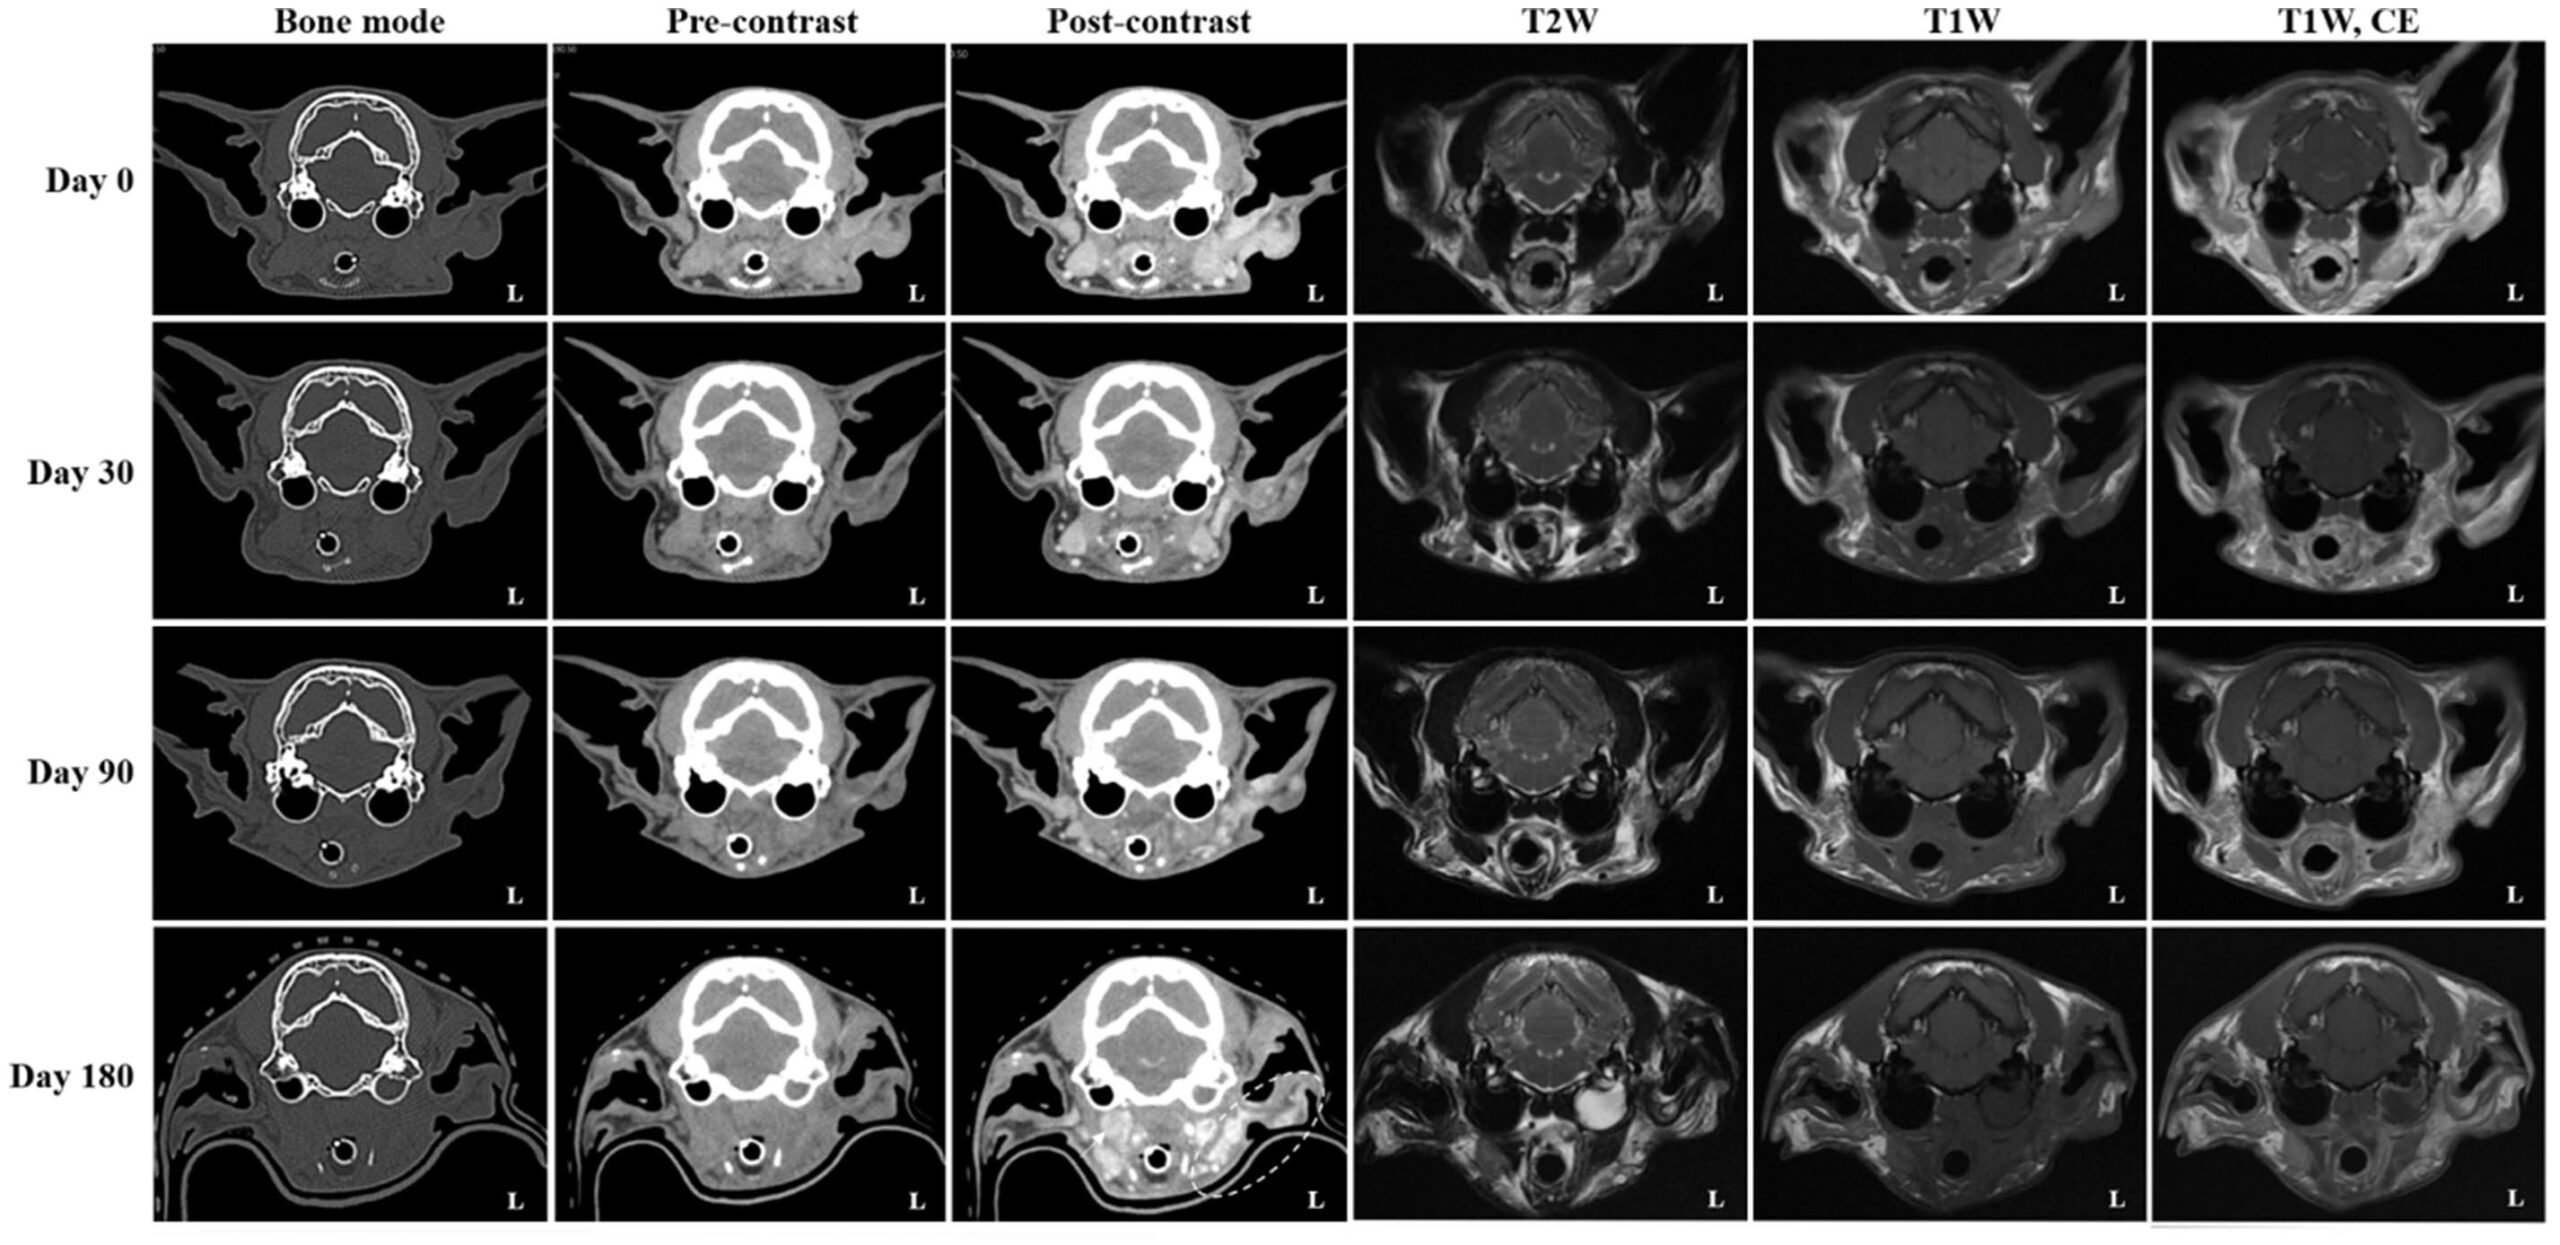

放疗后通过系列影像评估疗效与病情进展:分别于第0天(放疗结束)、第30、90、180天行CT及MRI复查,以监测治疗反应、残留病灶及肿瘤体积、局部侵犯和治疗相关并发症的变化。

第0天,影像显示左外耳道肿块体积显著缩小(图3),但外耳道内仍有残留软组织;此前侵及左腮腺及下颌区域的部分虽已明显回退,仍呈明显强化,边界不清,并推压邻近咬肌向内。同时可见外耳道壁增厚、钙化及少量腔内积液,符合外耳炎表现。左下颌、内侧咽后及肩前淋巴结仍肿大但较前明显缩小;右内侧咽后淋巴结轻度增大。

图3. 与治疗前(基线)相比,第0天肿瘤最大径缩小>50%,达部分缓解(PR);第30天再缩小约30%(累计约80%),维持PR;第90天仅再减小约10%,仍处PR;第180天病灶较最低点增大20%,伴区域淋巴结明显增大(箭头,左肩前淋巴结未示),符合疾病进展(PD)。同期CT及MRI见左鼓室积液,符合中耳炎;左腮腺及下颌区(虚线环)强化增加,疑肿瘤进展或复发。

第30天,CT/MRI示外耳道内肿块进一步缩小。尽管如此,左腮腺及下颌区仍持续可见强化且边界不清;下颌及咽后淋巴结虽继续缩小,仅余轻度增大,但左肩前淋巴结较前次扫描显著增大。DWI/ADC上,高信号灶的大小与信号强度与第0天相仿,平均ADC值320×10⁻⁶ mm²/s,大小11.03×6.41 mm。

第90天,残留灶的大小、范围及影像特征与第30天相比无明显变化;左肩前、下颌及内、外侧咽后淋巴结仍严重肿大,程度类似。DWI高信号灶亦保持稳定,平均ADC值448×10⁻⁶ mm²/s,大小11.13×10.17 mm。左腮腺与下颌区持续异常,提示存在残留肿瘤组织。

第180天,常规CT/MRI虽显示残留灶大小及范围无明显变化,但出现明显疾病进展:左内侧咽后、左肩前及右内侧咽后等多组淋巴结显著增大,左腮腺与下颌区强化程度增加,提示肿瘤可能复发或进展;同时新发左侧中耳炎。平均ADC值384×10⁻⁶ mm²/s,大小7.53×8.62 mm。

依据VCOG v1.0实体瘤疗效评价标准(以病灶最大径为参数):第0天肿瘤较基线缩小>50%,达部分缓解(PR);第30天再缩小约30%(累计约80%),维持PR;第90天仅再减小约10%,仍处PR;第180天病灶较最低点增大20%,伴区域淋巴结显著增大,符合疾病进展(PD)。